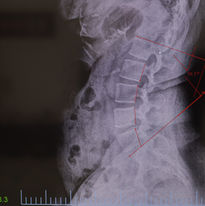

If required, we use digital X-rays to give you the most accurate care possible. These images allow Dr. Johnson to see things that are happening beneath the surface. Things like the curvature of your spine, condition of your joints, and health of your bones. Having a clear, detailed view helps us spot issues like misalignments, degeneration, or hidden injuries that a physical exam alone might miss.

While it can be intimidating to be X-rayed, this step can be important because these scans guide us in making the safest and most effective treatment decisions. They help us determine the right type of adjustment, whether additional therapies are needed, and how severe certain conditions might be. With this knowledge, Dr. Johnson can create a care plan that’s customized to your body and based on real evidence, not assumptions.

Thanks to modern technology, the X-rays we use are quick, comfortable, and involve minimal radiation exposure. And importantly for you, they allow you to see what Dr. Johnson sees. This gives you a better understanding of your own health, where you're making progress, and helping you to be an active partner in your healing process.